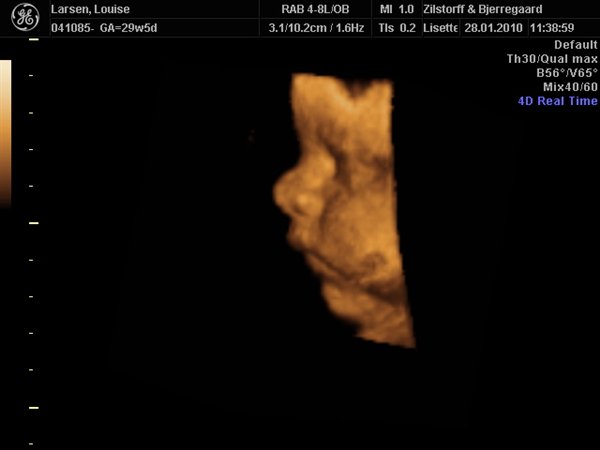

Vi har været til 3D/4D Scanning idag. Og sikke en vild oplevelse.... Har aldrig (udover min fødsel af Nicklas) prøvet noget så stort!

Her er lidt billeder: